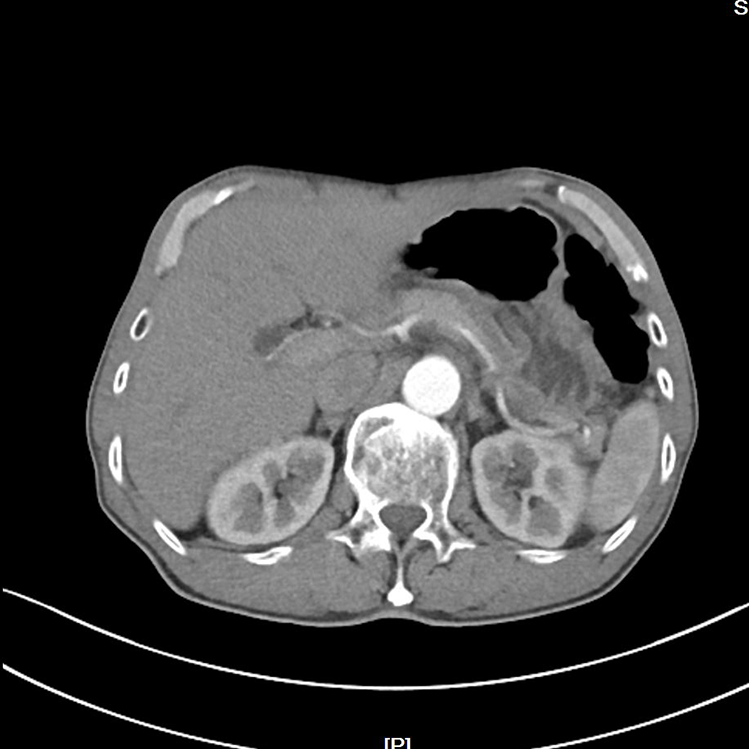

噩耗传来,老王确诊胃底腺癌,肿瘤进展累及胃食管结合部和食管下段,侵犯主动脉、腹腔干等血管,若立即手术,无法到达肿瘤R0切除,肿瘤残留短期内局部复发,影响患者预后。

▲新辅助治疗前